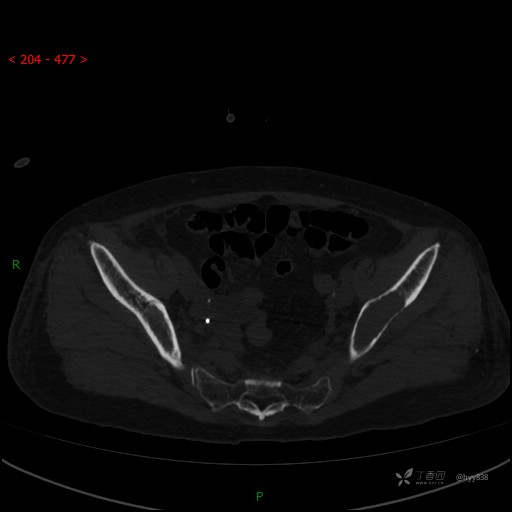

CT平扫

骨窗